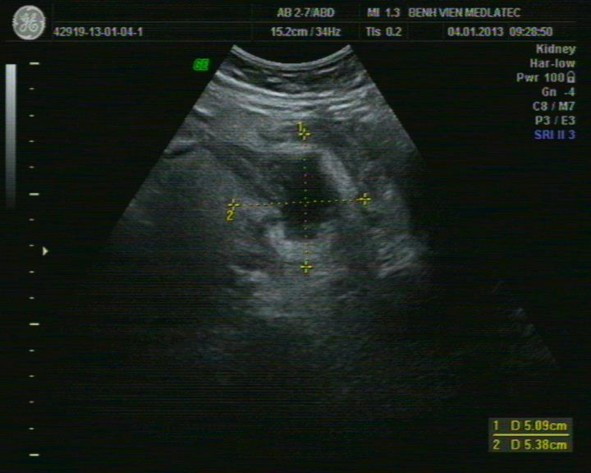

Hình 1.3 Hình ảnh áp xe ruột thừa trên siêu âm

* Nguồn BV Medlatec [17]

Do bản chất dịch nên hiện tượng tăng cường âm phía sau ổ áp xe rất rõ, dich mủ thường không có hồi âm hoặc lợn cợn hồi âm bên trong dịch, đôi khi có hiện diện của những bọt hơi đọng ở trên cao ổ áp xe hoặc rải rác trong dịch mủ của ổ áp xe. Khảo sát siêu âm Doppler cho thấy tình trạng sung huyết trên thành của ổ áp xe thể hiện sự gia tăng tín hiệu Doppler.